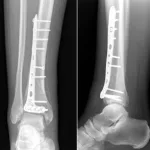

8時前に病棟に上がって, 昨日手術が行われた患者さん2人(外側半月板損傷に対する関節鏡下半月板縫合術, 脛骨遠位部骨折に対する骨折観血的手術)の経過を確認.

現在, 脛骨遠位部骨折の手術後で, 経過観察と骨粗鬆症の治療中でした.